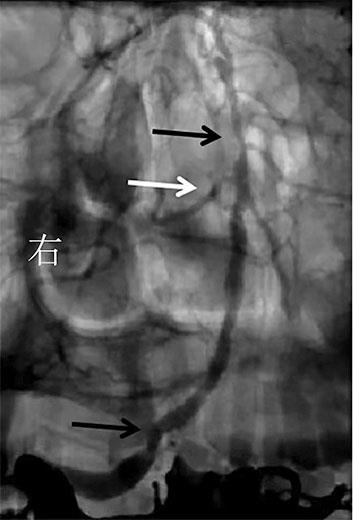

• 挽救性支架植入对取栓困难的脑动脉栓塞开通效果

2022, 47(7):779-783. DOI: 10.13406/j.cnki.cyxb.003067

摘要:目的 探究急性脑栓塞取栓失败和神经介入术中发生医源性脑动脉栓塞后补救性支架植入术的开通效果。方法 回顾性分析2020年1月至2021年11月上海交通大学医学院附属第九人民医院6例脑栓塞取栓失败和4例医源性颅内中远端动脉栓塞、接受补救性支架植入术的患者临床信息,总结患者术后血管开通情况、术后24 h 支架内血流通畅情况、出血转化和预后等情况。结果 6例急性脑栓塞取栓失败,补救性支架植入后闭塞血管全部开通(modified thrombosis in cerebral infarction score,mTICI 2b~3),术后3例出血转化(1例PH2型,2例HI2型),术后24 h支架内血流通畅5例(83%),1例未行血管造影复查;3例患者住院期间死亡。4例医源性中远端动脉闭塞中,1例为原发病为椎基底动脉高度狭窄,支架置入术中发生右侧小脑前下动脉闭塞,补救性支架置入后完全开通,术后24 h复查所有支架通畅,无脑出血,3个月预后良好,改良Rankin量表(modified Rankin score,mRS)评分1分;3例原发病为大脑中动脉栓塞,取栓术中出现同侧大脑前动脉分支闭塞,补救性支架植入后完全开通,其中1例术后24 h头颅计算机体层血管成像(computed tomography angiography,CTA)可见支架通畅,合并片状出血转化(HI2型),2例因为病重未行血管复查。结论 补救性支架植入可以快速开通取栓失败以及医源性中远端动脉的栓塞,但是疗效和安全性需进一步研究。